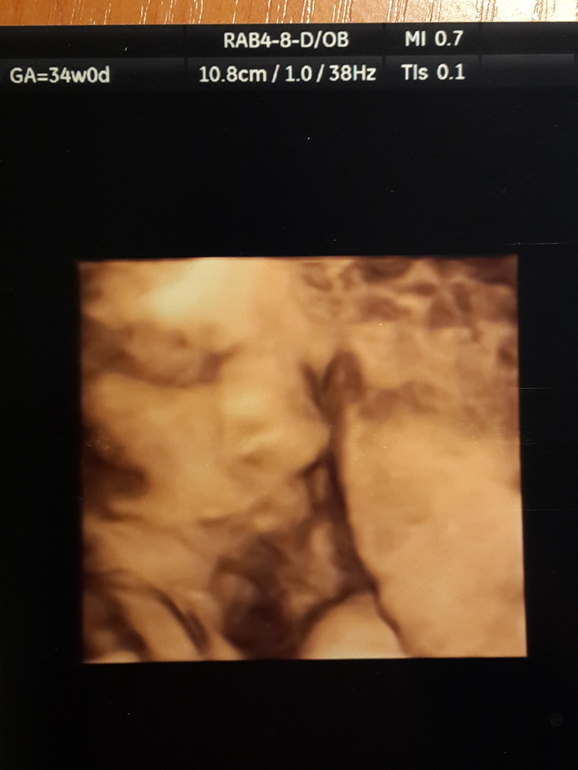

Какая же моя принцесса сладкая. Весим мы уже 2500, спрогнозировали,что к рождению будем где-то 3800... ой ёй)) ножки у нас длинные, сказали высокая будет)) в наши 34 недельки ножки аж на 37 и 6. А в среднем показатели соответствуют 35 нед. И наш ПДР передвинулся на неделю раньше, на 4 декабря. Лежит малышка вниз головкой, сказали что уже низко, поэтому и фото не получалось(( Но вот самое удачное